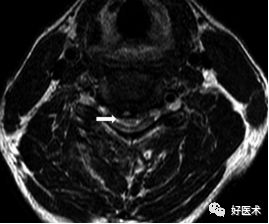

诊断